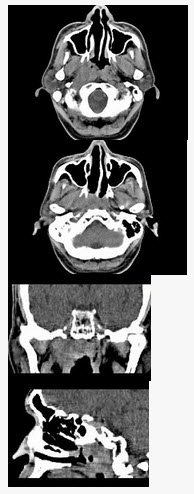

[单选题]男,52岁,血涕3月余。CT如图所示,最可能的诊断为()。A . 鼻咽癌B . 咽旁混合瘤C . 咽部神经纤维瘤D . 小唾液腺瘤E . 咽旁脓肿